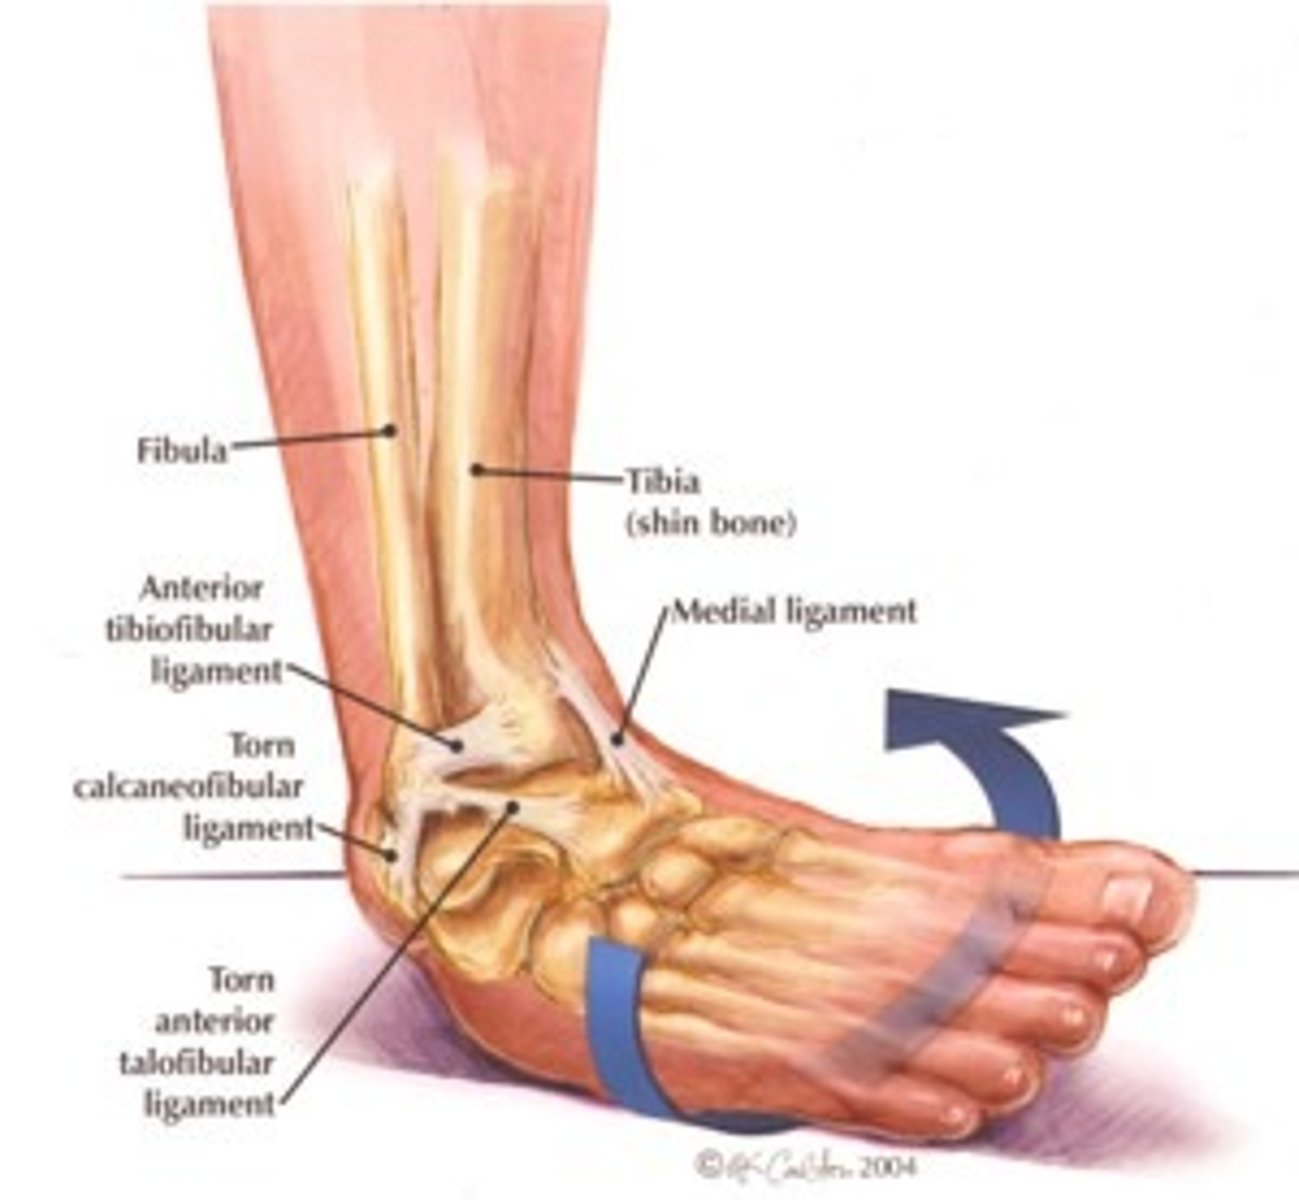

What ligament limits inversion and dorsiflexion?

Calcaneofibular ligament

What ligament limits inversion and plantarflexion?

Anterior talofibular ligament

Most frequently injured ligament in ankle and foot complex

Most common injury mechanism for anterior talofibular ligament sprain

Inversion + plantarflexion during weight bearing

The relative inability of the _______ ________ to block the medial side of mortise joint contributes to anterior talofibular ligament sprains.

Medial malleolus